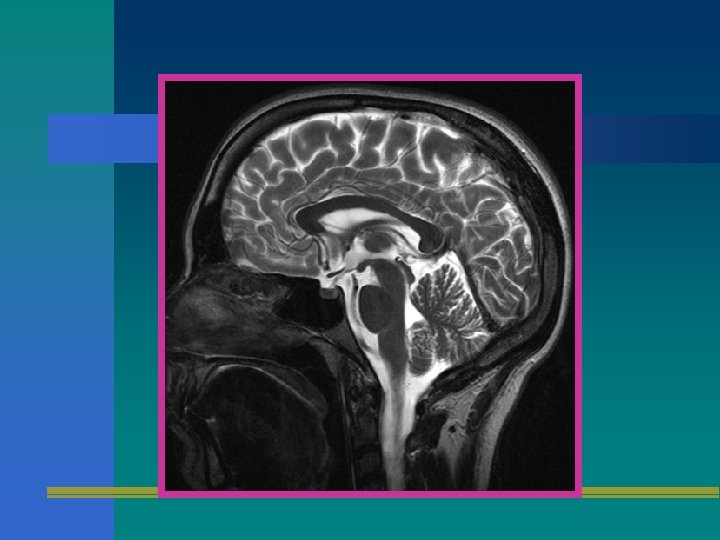

SECUENCIA T 2 • UTILIZA UN ECO SPIN CON TE LARGO Y TR LARGO. • ES MUY SUSCEPTIBLE A LOS CAMBIOS EN EL CONTENIDO DE AGUA Y POR ENDE AL EDEMA Y LA INFLAMACION.